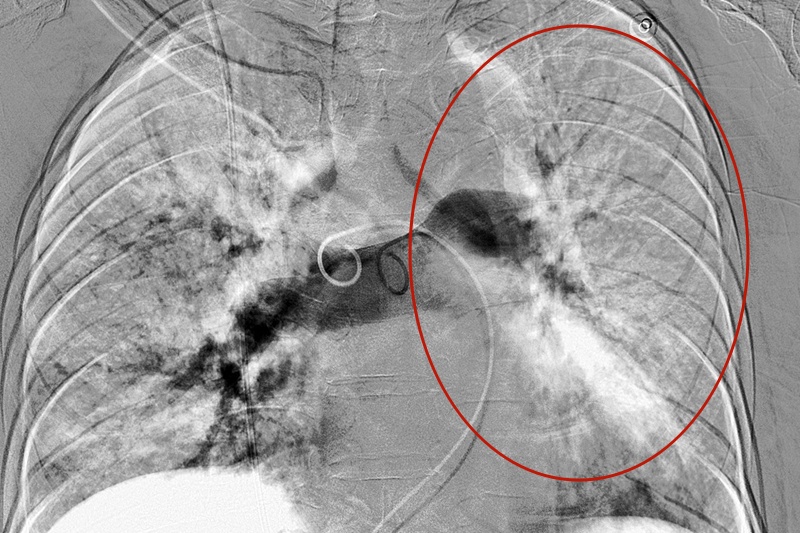

【术前闭塞的肺动脉】

【术后肺动脉血流恢复】

原先完全闭塞的左肺动脉在抽栓后,明显恢复血流。患者呼吸困难症状迅速缓解,血压及血氧饱和度恢复正常水平。